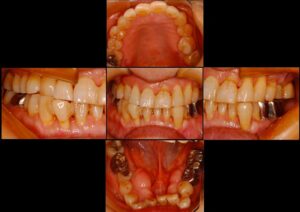

• 前回の続きのインプラント矯正

前回の続きのインプラント矯正

前回のブログで、ミニインプラントを使った矯正のお話をしましたが、治療が終了しましたので、お知らせします。 治療開始前はこんな感じで、前歯の下側を真っすぐにしてほしいという希望でした。 奥歯が前に倒れ過ぎていて、そこをかなり後ろにさげながら起 […] 本文を読む